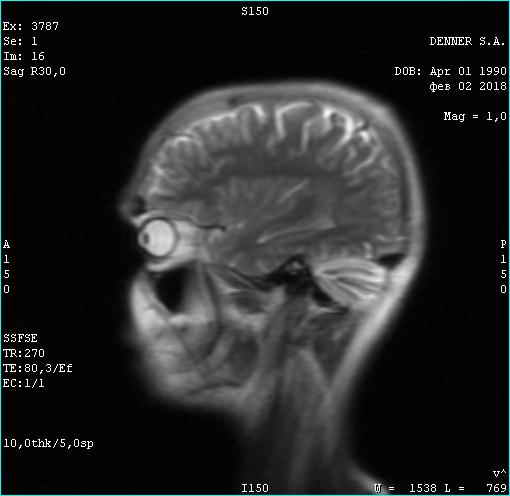

Фома неверующий. Вот этого парня я сейчас лечу. Опухоль за 3 месяца лечения уже не активна. Частично пошло ее разложение. Тремор сердца исчез. Походка восстановилась. В августе скину новое мрт с результатом лечения. Динамика на снимке. Ядро опухоли гибнет за 3 месяца. Господа!!!! За 3 месяца!

Тип файла: jpeg 02.02.2018.jpeg (22.5 Кб, 704 просмотров)

Вверху февраль 2018. Внизу май 2018

Опухоль контраст не накапливает. Связи с костью уже не имеет. Головка опухоли начала разлагаться. Врачи в шоке. А я злорадствую. Сергей мне поверил и сейчас копает огород на Алтае, хотя должен был умереть в июле. Моя карма получила жирный плюс...

Фото мрт сделаны немного в разных ракурсах, (зачем, непонятно-наверное чтобы не признавать эффект оздоровления ), но положительная динамика все равно видна. И пациент начал жить полноценной жизнью - секс, загар, копание огородов и рыбалка...